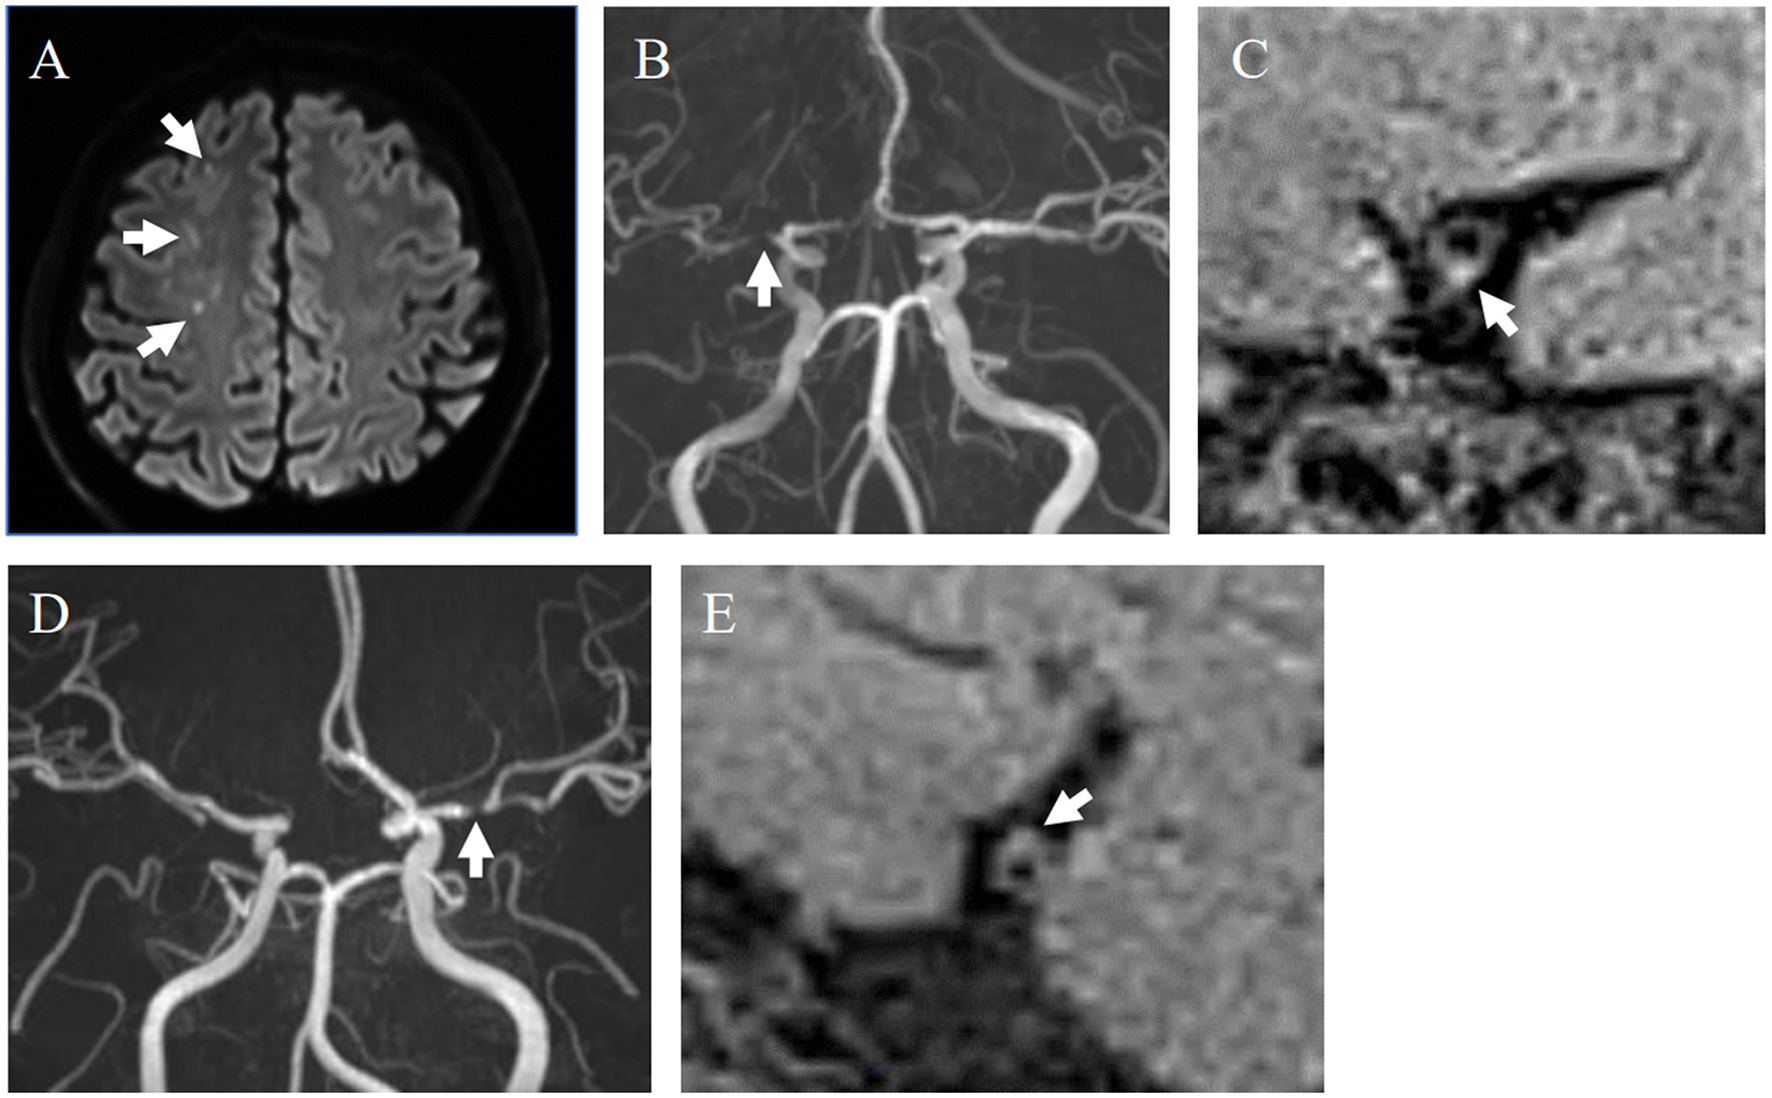

All plaques were divided into symptomatic and asymptomatic groups. A plaque was considered symptomatic when it satisfied one of the following criteria: (1) presence of a hyperintense area on DWI within the territory supplied by the stenotic artery; (2) transient ischemic attack (TIA) with symptoms associated with the cerebral region supplied by the stenotic artery within the 4 weeks preceding the MRI examination, with no acute ischemic lesions detected on DWI. Furthermore, the symptomatic cases were subdivided into five subgroups: (a) artery-to-artery (A-to-A) embolism, defined as more than two hyperintense lesions on DWI detected in the territory supplied by the stenotic artery. Moreover, SPECT showed that the resting CBF in this territory was >80% of the normal value, atrial fibrillation (AF) was not detected by an electrocardiogram (ECG), and transthoracic echocardiography showed no intracardiac thrombi. (b) Hemodynamic infarction, defined as more than two hyperintense lesions on DWI detected in the territory supplied by the stenotic artery, with stenosis ≥70%, SPECT showing resting CBF in the territory <80% of the normal value, and cardiac embolism was excluded as described above. (c) Perforator infarction: a single hyperintense lesion on DWI detected in the perforating artery territory (internal capsule, basal ganglia, and corona radiata) supplied by the stenotic artery, and stenosis located proximally to the bifurcation of the perforator. (d) Undetermined lesions: hyperintense lesions detected on DWI when the first three cases were excluded. This category included suspected cases of cardiac embolism, in which AF was detected on ECG, according to the TOAST classification (Adams et al., 1993). (e) TIA cases without DWI lesions were in the fifth subgroup same as (2) above. The proportion of HIPs was calculated for the overall symptomatic and asymptomatic groups, as well as for each of the five subtypes within the symptomatic group. Two representative cases with and without a HIP are shown in Figure 1.

Representative cases with and without HIPs. (A–C) A 40-year-old male with symptomatic stenosis in the right MCA. (A) Multiple cerebral infarcts were detected in the right cerebral white matter on DWI (white arrows). (B) MRA showed severe stenosis of the M1 segment of the right MCA (white arrow). (C) An HIP was detected on the sagittal section of the MCA on DANTE T1-SPACE (white arrow). SIplaque/SImuscle ratio was 1.61. This case was diagnosed as A-to-A embolism. (D, E) 59-year-old female with asymptomatic stenosis in the left MCA. (D) MRA showed severe stenosis of the M1 segment of the left MCA (white arrows). (E) The plaque without hyperintensity was detected on the sagittal section of the MCA on DANTE T1-SPACE. SIplaque/SImuscle ratio was 1.33.